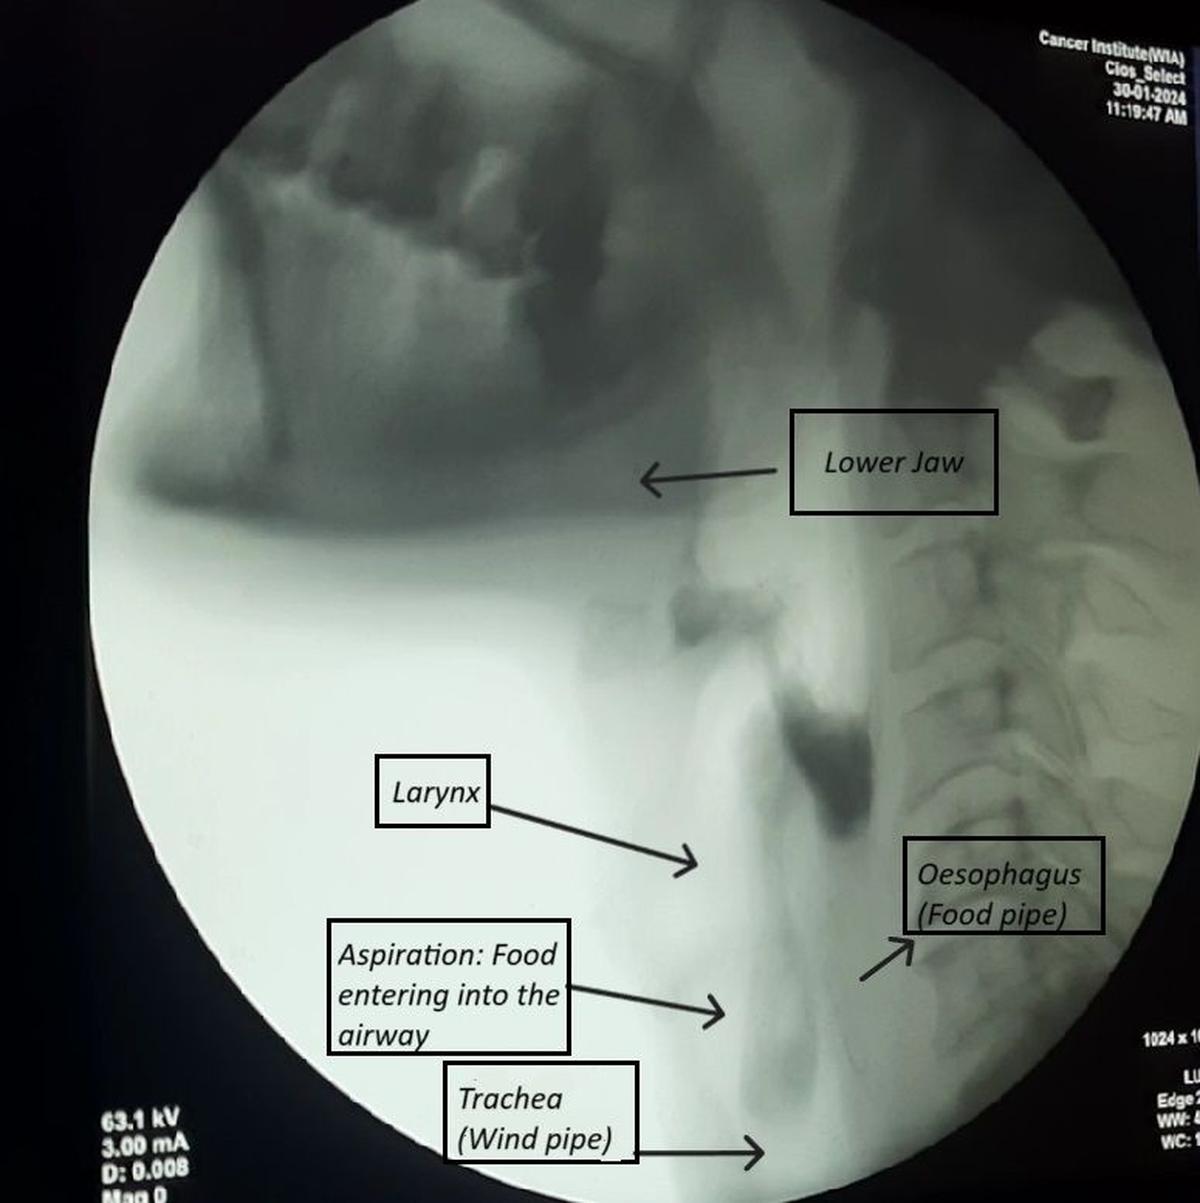

Balsene ir niecīgs orgāns, kas sēž elpceļu un pārtikas fragmentu krustojumā. Ēdiens, ko mēs ēdam, un gaisu, kuru mēs elpojam, braucot blakus, piemēram, paralēli dzelzceļa sliedes ar krustojumu. Mūsu balsenes tuvums pārtikas caurulei (barības vads) un tā stratēģiskā pozīcija vēja caurules izcelsmē (traheja) ļauj tam būt elpceļu galveno vārtu turētājam. Larynx darbojas kā svira, kas atveras elpošanai, vibrē runai un aizver elpceļus klepus laikā un norijot, tādējādi aizsargājot elpceļus no pārtikas un šķidrumu dilstošās bolus, bloķējot tā iekļūšanu vēja caurulē. Kad šī funkcija tiek apdraudēta, pārtika var nonākt nepareizā fragmentā un pēc tam mūsu plaušās (komplikācija, kas pazīstama kā aspirācija) un var potenciāli izraisīt dzīvībai bīstamas komplikācijas, ieskaitot aizrīšanos un pneimoniju.

Video-fluoroskopiskais bezdelīgas pētījums (VFSS) tiek uzskatīts par zelta līmeņa rīšanas novērtēšanas standartu, kas var vizualizēt visus pārtikas tranzīta posmus reālā laika rīšanas procesā. Šis attēls uztver pārtikas bolus, kas pasniegts pacientam ar rentgenogrāfisku kontrastu, attēlu sānu (sānu skatījumā) skatu uz galvas un kakla reģionu. Pēc bezdelīgas pabeigšanas, ideālā gadījumā, nevienam ēdienam nevajadzētu palikt rīklē. Tomēr šis attēls attēlo atlikušo pārtiku rīklē rīšanas beigās, izraisot aspirāciju, kad pārtikas materiāls izplūst elpceļā. Šis ir viens no uzlabotajiem instrumentālajiem novērtējumiem, ko veic SLP, lai iegūtu precīzu diagnozi.